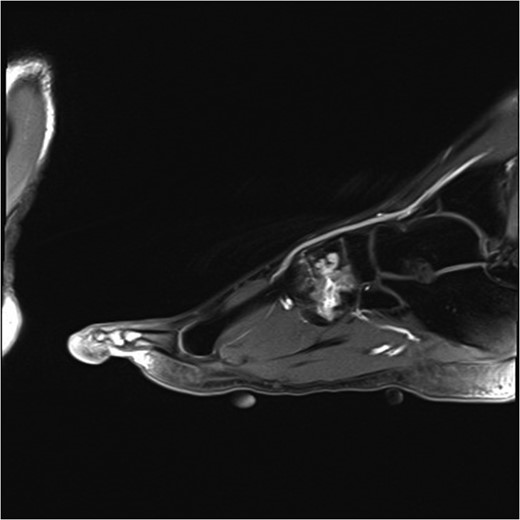

The patient had an magnetic resonance (MR) angiogram and Doppler US to investigate the lesion further. MR angiogram demonstrated high signal in the intermediate and lateral cuneiform bones in keeping with vascular malformation (Fig. 3). US confirmed an abnormal communication between metatarsal artery and vein at sites in foot where he experienced most pain. These images were discussed at a joint vascular and plastics MDT where a diagnosis of an AVM was concluded.

MRI angiogram of left foot. High signal in the midfoot bone around the intermediate and lateral cuneiform bones in keeping with a venous malformation.